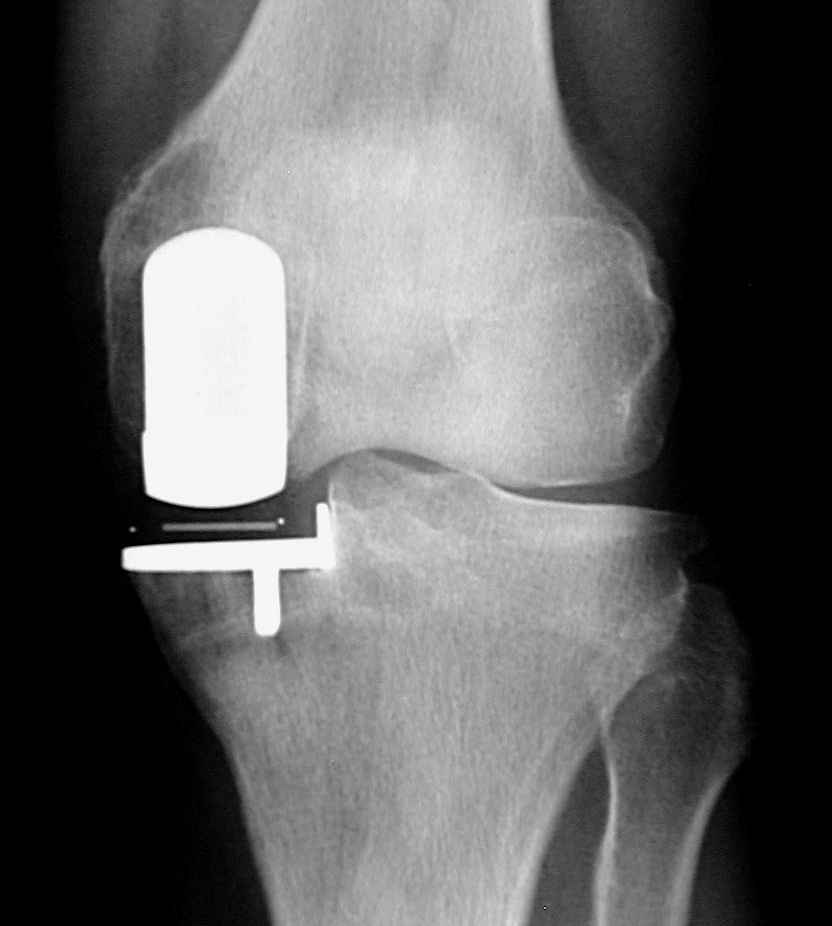

(“鑲牙”似的單髁置換術(shù)后X光片)

微創(chuàng)膝單髁置換術(shù)與全膝關(guān)節(jié)置換術(shù)相比,優(yōu)勢(shì)十分明顯。微創(chuàng)膝單髁置換術(shù)具有手術(shù)切口小,損傷小,出血少,無(wú)需輸血;術(shù)后疼痛少,術(shù)后第2天即能下地行走,術(shù)后3天可以出院。2017年6月以來(lái),柳州市人民醫(yī)院關(guān)節(jié)骨病運(yùn)動(dòng)醫(yī)學(xué)科以彭偉秋博士為首的團(tuán)隊(duì),積極學(xué)習(xí)和引進(jìn)新技術(shù),在柳州市率先成功開(kāi)展了膝關(guān)節(jié)單髁置換手術(shù)。柳州380萬(wàn)人口中20%是60歲以上老人,76萬(wàn)老人中約有50萬(wàn)老人患有老年性膝骨性關(guān)節(jié)炎,其中3%是處于晚期。由于晚期老年性膝骨性關(guān)節(jié)炎致殘,病人無(wú)法生活自理,給家庭和社會(huì)帶來(lái)了較重的負(fù)擔(dān)。我院開(kāi)展的微創(chuàng)膝單髁置換術(shù)實(shí)現(xiàn)了對(duì)晚期膝骨性關(guān)節(jié)炎的精準(zhǔn)優(yōu)化治療,具有康復(fù)快,療效優(yōu),病人樂(lè)意接受等特點(diǎn),為保障老百姓的健康提供了新方案。